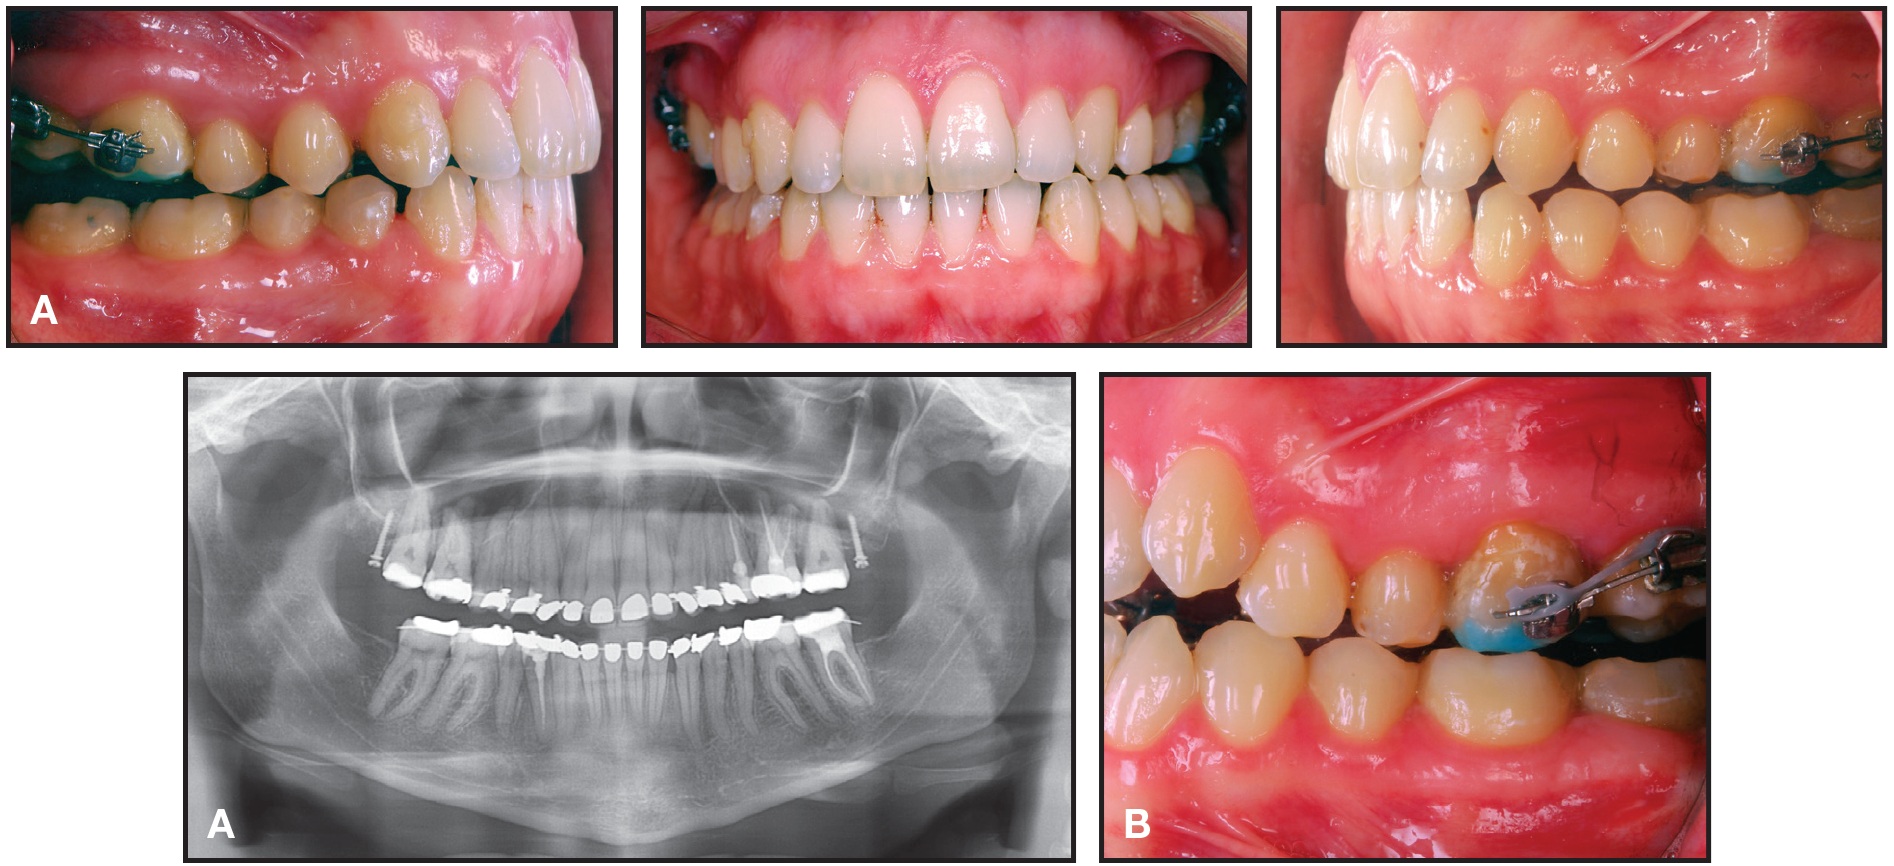

A 25-year-old female patient presented with a skeletal Class II pattern, Class II molar and canine relationships (complete on the left and edge-to-edge on the right), excessive overjet, and a narrow maxilla (Fig. 1).

Fig. 1 25-year-old female patient with skeletal Class II pattern, excessive overjet, and anterior open bite before treatment.

Her mouth-breathing habit had caused gingivitis of the upper incisors, and her vertical mandibular plane had led to lip incompetence that made it difficult to close her lips at rest. She displayed an open bite from premolar to premolar, a crossbite on the left side, and moderate crowding of the upper and lower anterior teeth. The upper and lower occlusal planes were tilted from left to right, causing the mandible to show a slight deviation to the left. The upper third molars were present, but the lower right had been extracted and the lower left was mesially impacted.

Two Dual-Top* JA standard mini-implants (1.6mm x 10mm) were placed distal to the second molars in the maxillary tuberosities (Fig. 2). One and a half months later, since the patient wanted to be treated with invisible appliances, the Incognito** lingual system was bonded and an .014" nickel titanium archwire was inserted (Fig. 3). This appliance is compatible with skeletal anchorage and has proven reliable in complex treatments. Gentle force was applied with elastic chain from the miniscrews to distalize the upper teeth. To prevent undesirable transverse movement of the molars, tubes or brackets were bonded to the buccal surfaces of the first and second molars and connected by sectional .016" x .022" nickel titanium wires.

In less than a year of treatment, the anterior open bite was closed and the molar Class II malocclusion improved, but a posterior open bite had been created (Fig. 4A). Comparing the initial panoramic x-ray and a progress x-ray taken at that time, there was a considerable reduction in the distance between the upper second molars and the mini-implants, demonstrating a bodily maxillary retraction.

Fig. 2 Six months after extraction of upper third molars, one Dual-Top* mini-implant placed in each maxillary tuberosity.

Fig. 3 One and a half months later, Incognito** lingual bracket system bonded, .014" nickel titanium archwire inserted, and gentle forces applied with power chain from miniscrews to distalize upper teeth. Tubes or brackets bonded to buccal surfaces of first and second molars and sectional .016" × .022" nickel titanium wires placed to prevent undesirable transverse movement.

Fig. 4 After 10 months of distalization. A. Distance between miniscrews and second molars reduced substantially and Class II malocclusion improved, but posterior open bite created due to direction of forces. B. Power chain passed buccally over molar tubes to help control bodily movement and prevent undesirable vertical movement.